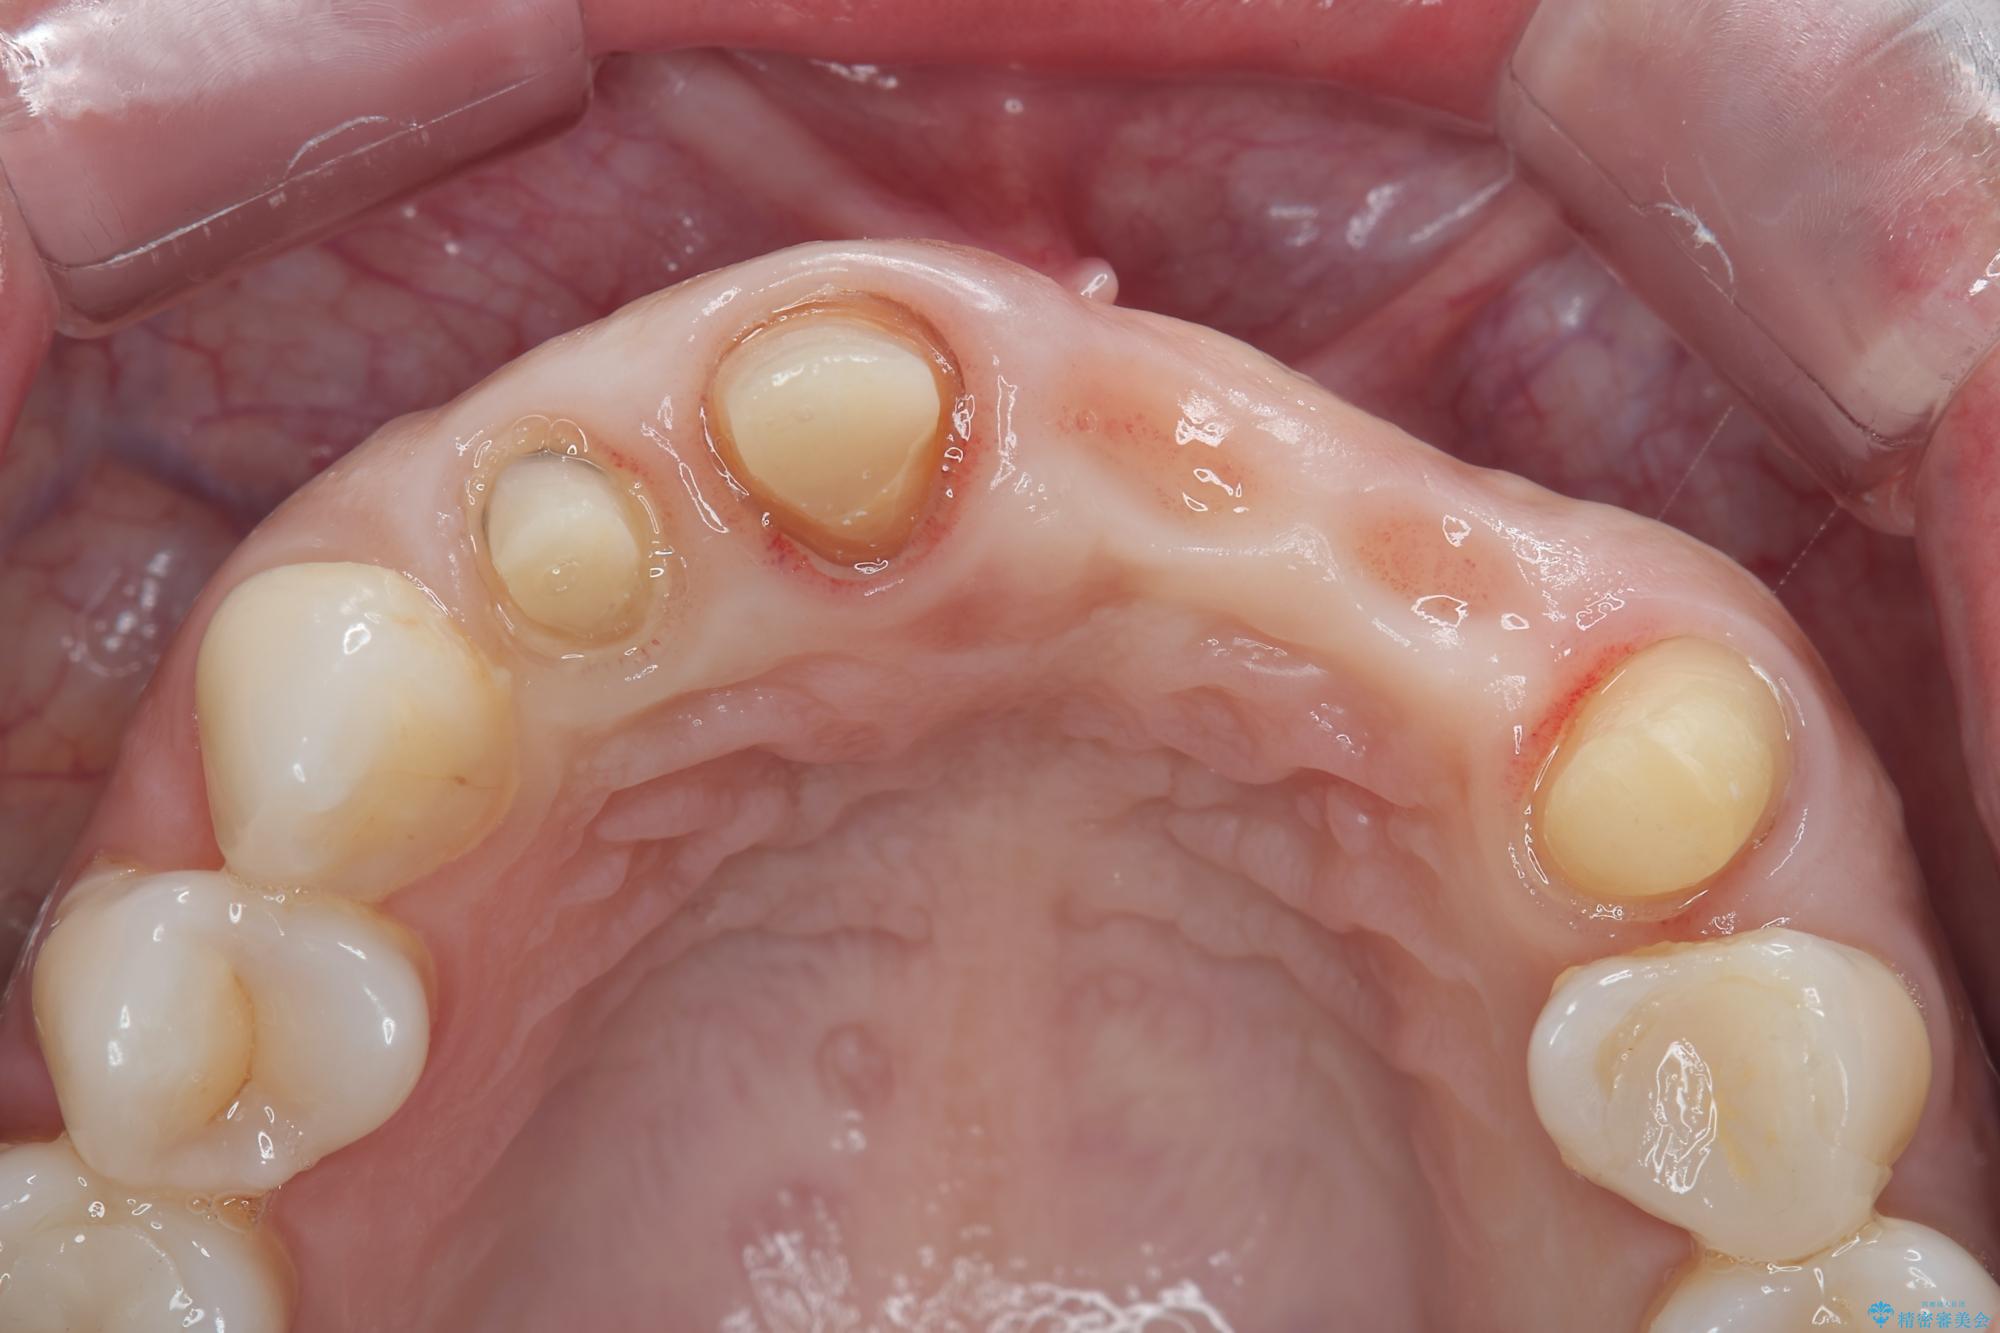

一見して問題ないように見える左側の2前歯は、セラミックを除去してみると亀裂や虫歯の再発が見られました。

治療前

歯槽堤保存術を併用したブリッジ治療 治療前画像 歯槽堤保存術を併用したブリッジ治療 治療前画像 歯槽堤保存術を併用したブリッジ治療 治療前画像 歯槽堤保存術を併用したブリッジ治療 治療前画像 歯槽堤保存術を併用したブリッジ治療 治療前画像 歯槽堤保存術を併用したブリッジ治療 治療前画像 歯槽堤保存術を併用したブリッジ治療 治療前画像 歯槽堤保存術を併用したブリッジ治療 治療前画像 歯槽堤保存術を併用したブリッジ治療 治療前画像 歯槽堤保存術を併用したブリッジ治療 治療前画像